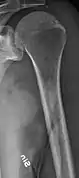

The diagnostic examination of a person with suspected multiple myeloma typically includes a skeletal survey. This is a series of X-rays of the skull, axial skeleton, and proximal long bones. Myeloma activity sometimes appears as "lytic lesions" (with local disappearance of normal bone due to resorption) or as "punched-out lesions" on the skull X-ray ("raindrop skull"). Lesions may also be sclerotic, which is seen as radiodense.[70] Overall, the radiodensity of myeloma is between −30 and 120 Hounsfield units (HU).[71] Magnetic resonance imaging is more sensitive than simple X-rays in the detection of lytic lesions, and may supersede a skeletal survey, especially when vertebral disease is suspected. Occasionally, a CT scan is performed to measure the size of soft-tissue plasmacytomas. Bone scans are typically not of any additional value in the workup of people with myeloma (no new bone formation; lytic lesions not well visualized on bone scan).

Multiple myeloma in the upper arm